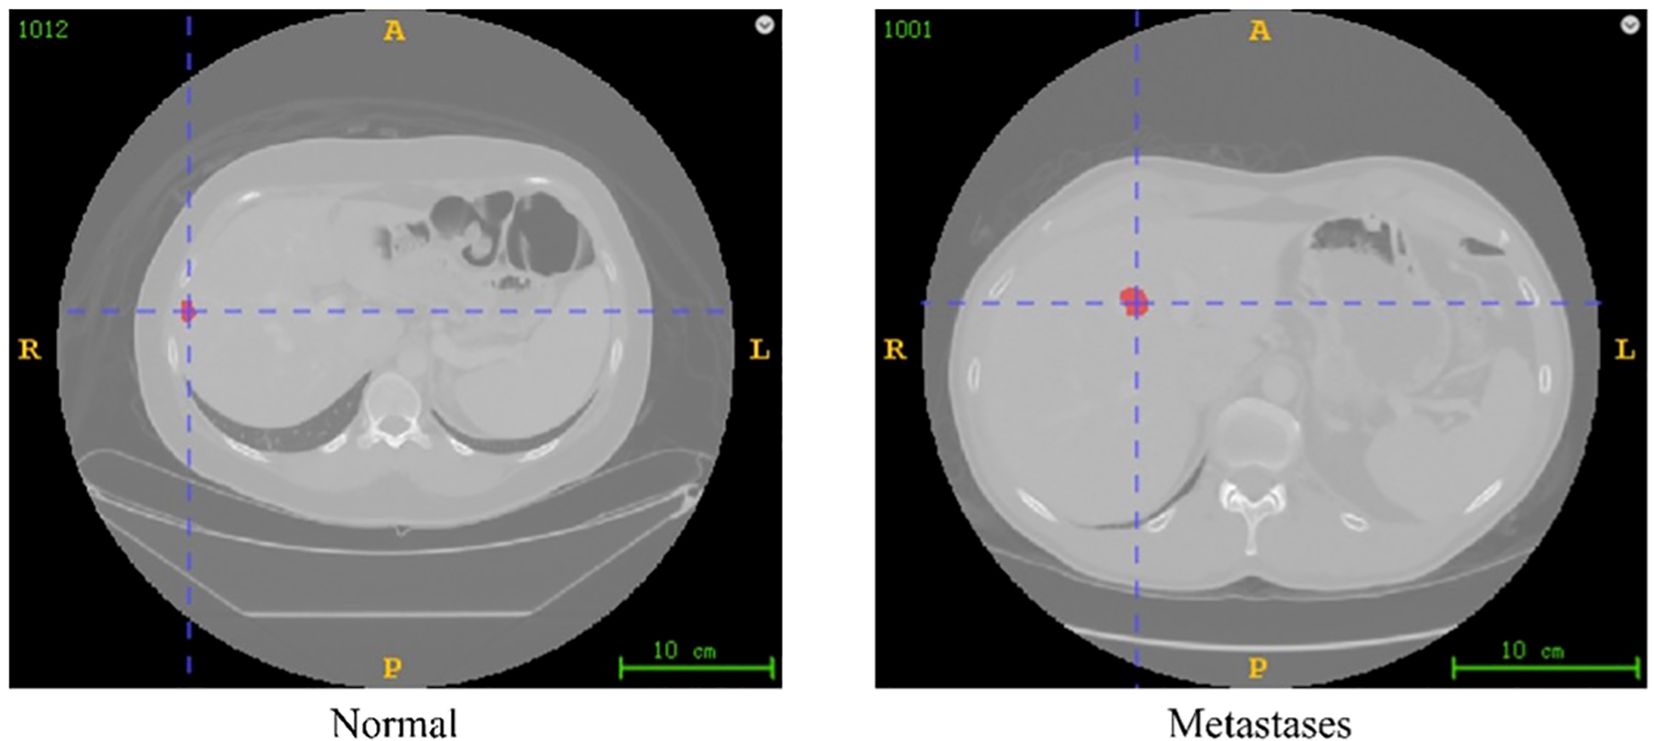

Background: The overall incidence of liver metastasis in colorectal cancer is as high as 50%, and surgery remains the only potentially curative approach for the metastatic disease. The recurrence rate of liver metastases within one year after surgery is still 60%-70% in clinical practice. Whether we can accurately predict the early recurrence of patients after surgery is one of the most important considerations in formulating the overall treatment strategy. Methods: In this study, we combined radiomics feature extraction with machine learning classification methods to develop a novel strategy for predicting intrahepatic metastases based on imaging radiomics and machine learning. We constructed and systematically evaluated multiple machine learning models to assess their performance. By validating these models on a test set, we determined the effectiveness of each predictive model and selected the one with the highest predictive accuracy. Results: The integration of radiomics and machine learning methods demonstrated significant potential in predicting intrahepatic recurrence within one year after surgery in patients with colorectal cancer liver metastases. The Gradient Boosting, LightGBM, and Random Forest models all achieved classification accuracies (ACC) exceeding 65% across all classification tasks. Notably, the Random Forest model exhibited the best performance; while its classification accuracy was 65.52% in the imaging-only group, it increased to 75.86% when both imaging and clinical information were combined, with an area under the receiver operating characteristic curve (AUC) of 70.83%, indicating strong predictive capability. These findings suggest that these models have potential application value in supporting the diagnostic work of clinical radiologists, potentially helping to reduce workload and decrease the risk of misdiagnosis. Conclusions: The imaging omics model and the combined model have good predictive efficacy for the recurrence of colorectal cancer liver metastases within one year, and can be used to assist in the clinical stratification of postoperative patients and identify high-risk factors for poor prognosis.